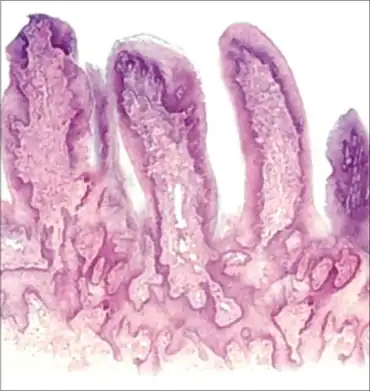

| Digitate structures of loosely arranged subdermal tissue | |